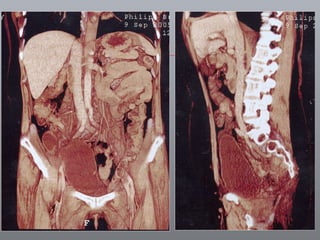

Câncer de Bexiga Estudos de imagens Diagnóstico Ultrassonografia Urografia excretora Estadiamento CT RNM Rx tórax  Cistoscopia + biópsia + biópsias randomizadas

CT